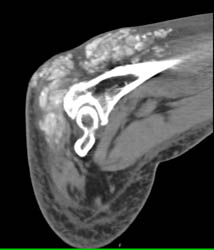

Gout